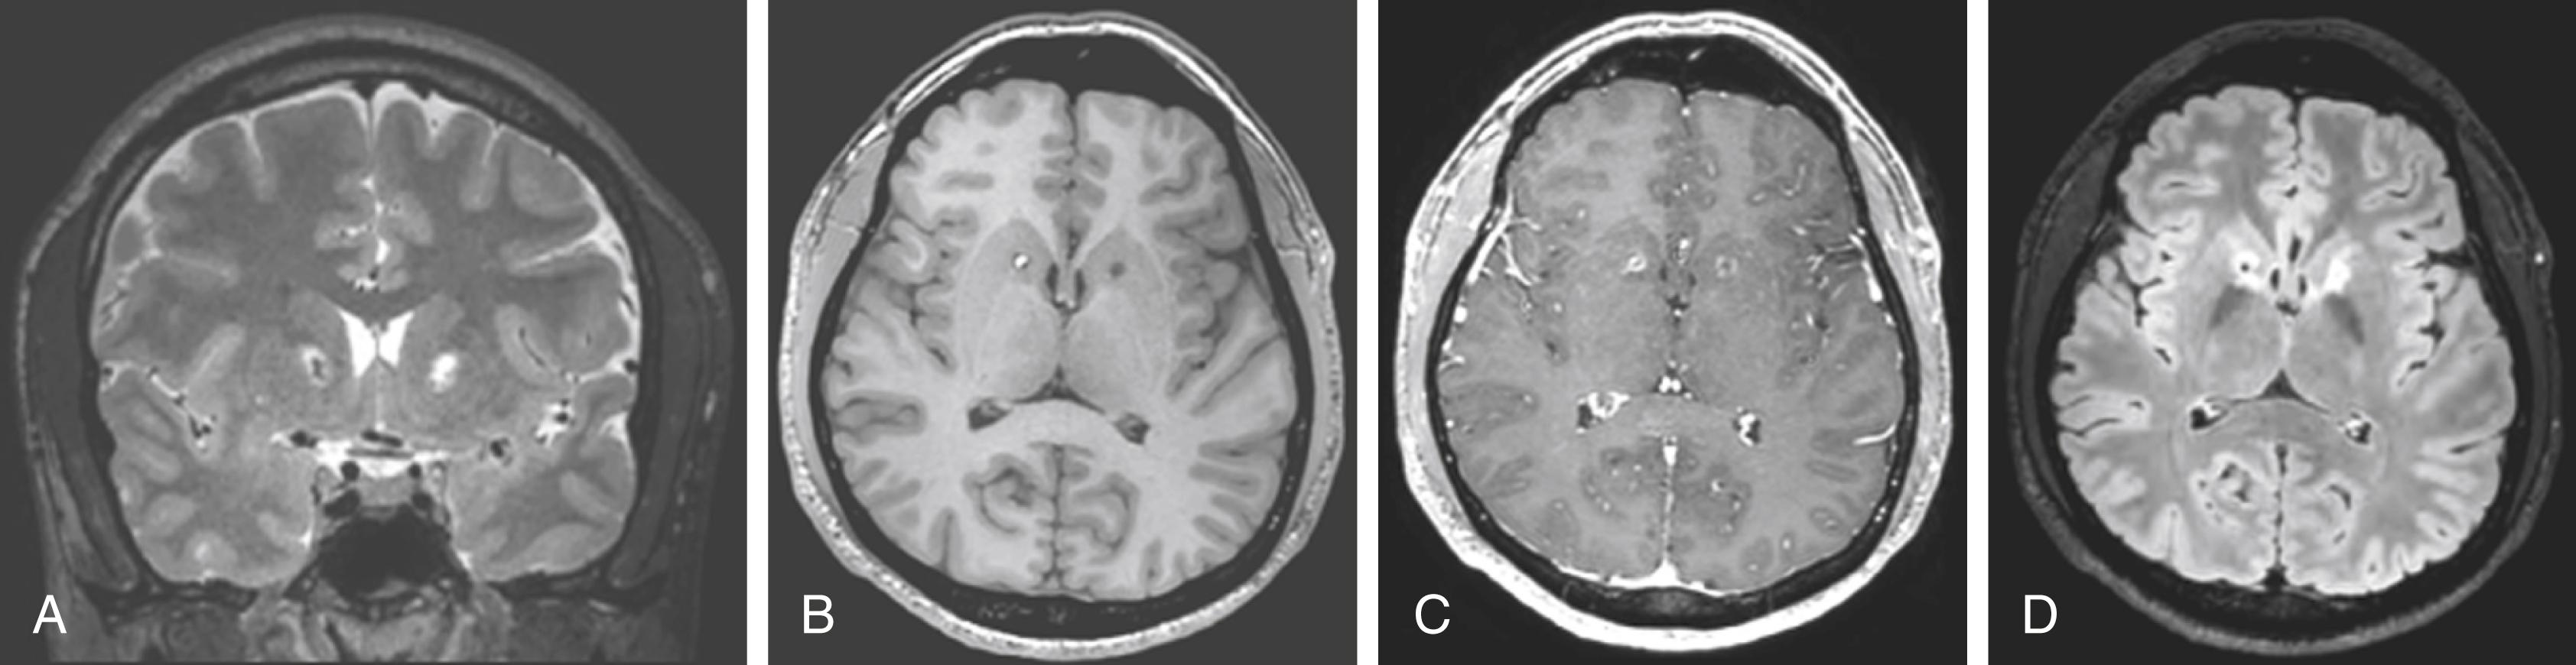

Current work in this field seeks to balance the high efficacy rate of previous studies against the desire to lower the adverse event rate. One such attempt involves the creation of novel radiosurgical plans that recapitulate the volume covered by the double shot at high isodose lines but avoids larger volumes at lower isodose lines. These larger volumes at lower dose are thought to be responsible for the radiation-induced edema and cyst formation seen in occasional patients. Shaping and blocking strategies can be used to sharpen the dose falloff and improve the dose-volume relationships, although the trade-off is longer treatment time. Preliminary results from such a plan used in five patients, with an effective two-shot 150-Gy maximum dose configuration and conformal distribution, have produced three responders at 1-year follow-up, with no evidence of edema on MRI and no adverse neuropsychological sequelae ( Fig. 109.2 ).

FIGURE 109.2, Gamma Knife capsulotomy neuroimaging. Lesions from bilateral Gamma Knife capsulotomy are show in the (A) coronal plane with T2-weighted imaging, (B) axial plane with T1-weighted imaging, (C) axial plane with T1-weighted imaging with contrast, and (D) axial plane with fluid-attenuated inversion recovery imaging.